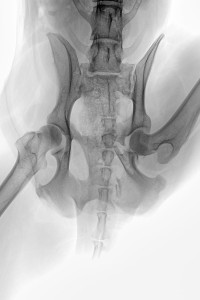

Die Aufnahme vom 04. Nov. zeigte bereits eine beginnende Kallusbildung und mit Absprache des Orthopäden wurde ab dem 03. Dez. mit Physiotherapie, d.h. Unterwasserlaufband begonnen. Fast zeitgleich konnten wir ab Mitte Dez. Ihr Ergodyn VET-Line Gerät zum Einsatz bringen. Die Physiotherapie erfolgte zunächst nur einmal pro Woche, aber das Ergodyn haben wir fast täglich an den Hund angelegt. Beginnend mit 5 Minuten und steigernd auf 15 Minuten.